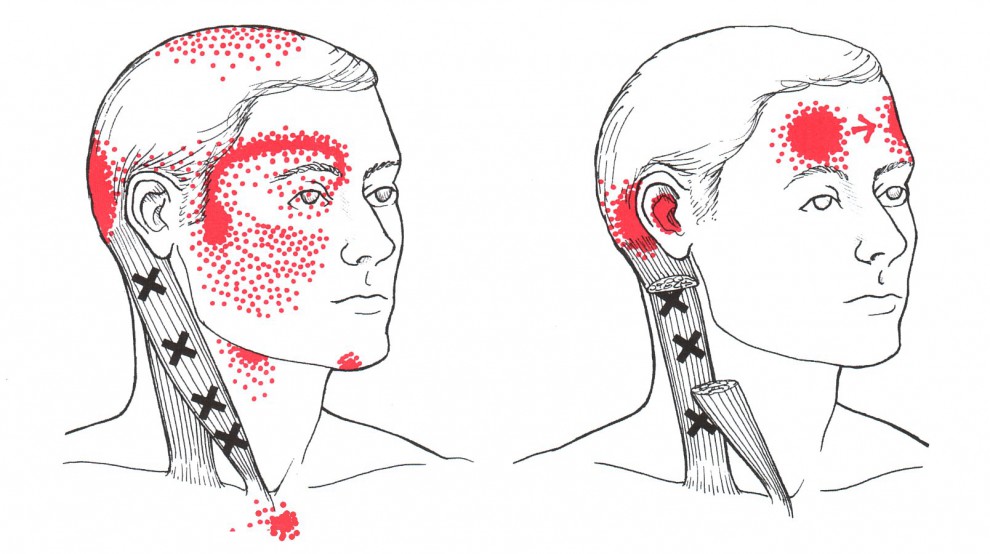

Cervikogenní bolesti hlavy jsou doprovázeny změnou tonu šíjového svalstva. Významnou roli mají především krátké suboccipitální svaly (krátké extenzory šíje) a jejich přetěžování právě v důsledku předsunutého držení hlavy. Dále jsou přítomny bolestivé spoušťové body v m.sternocleidomastoideus, mm.scaleni, ale také v m.trapezius či m.levator scapulae. Při tlaku na TrP v uvedených svalech bolest vyzařuje do do týla, oblasti spánků nebo temene, někdy až do čelní krajiny či retrobulbárně (za oči).

Obr. 5: TrPs v m.sternocleidomastodeus a jejich projekce bolesti

(zdroj: http://fortefitness.com/trigger-point-for-tension-headaches-stiff-necks-tmj)